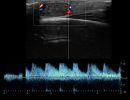

Η τεχνική του Έγχρωμου Doppler μελετάει την αγγείωση της βλάβης. Η τεχνική του Παλμικού Doppler μελετάει την παρουσία αρτηριακών ή φλεβικών στοιχείων εντός της βλάβης. Επίσης πολύ χρήσιμη είναι η Ελαστογραφική Μελέτη η οποία μελετάει τη σκληρότητας της βλάβης. Οι τεχνικές αυτές μας βοηθούν να χαρακτηρίσουμε αν η βλάβη είναι αγγειακού τύπου και αν έχει καλοήθη η ύποπτα χαρακτηριστικά.